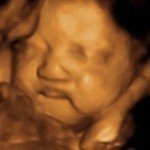

Monmouth County’s First 4D/5D/HD Live Ultrasound Studio

4D/5D/HD Ultrasound Gallery

Gallery